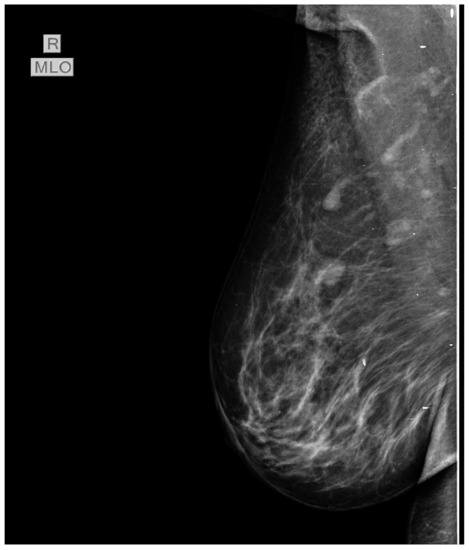

In July 2015 the patient was referred to our oncology clinic for management of an orbital metastasis with primary breast cancer. She was in a good general health status, had normal weight and Eastern Cooperative Oncology Group (ECOG) 0. Clinical examination of the breasts revealed a palpable mass of 2.5/3 cm in size in the left upper outer quadrant and the enlargement of ipsilateral axillary lymph nodes (cN1). In the upper internal quadrant of the right breast a tumor of 1.5/1 cm with a firm consistency and a smooth surface is palpated. The value of carbohydrate antigen 15-3 (CA 15-3) was 53 U/mL (normal values < 28 U/mL). Subsequently, standard mammography and bilateral breast echography were performed. Mammography showed in the upper external quadrant of the left breast a density asymmetry, with multiple micro-calcifications and associates multiple axillary adenopathies without the visualization of the fatty hilum (Figure 3). On the upper internal quadrant of the right breast, mammography also revealed an oval shaped image with benign characteristics suggestive for a fibroadenoma (Figure 4). Breast ultrasound revealed the left breast discerned an inhomogeneous hypoechogenic area of 23/22 mm, imprecisely delimited in the upper external quadrant and ipsilateral adenopathies. Breast imaging reporting and data system score (BIRADS) was 5 for the left breast, suggestive of malignancy. For the right breast, the BIRADS score was 2 with a suggestive aspect of mammary fibroadenoma. The established clinical diagnosis for this stage was: left superior external quadrant breast cancer cT2 cN1 pM1 stage IV.

Figure 4. Mammography also revealed in the upper internal quadrant of the right breast, an oval shaped image, well circumscribed, with benign characteristics suggestive for a fibroadenoma.